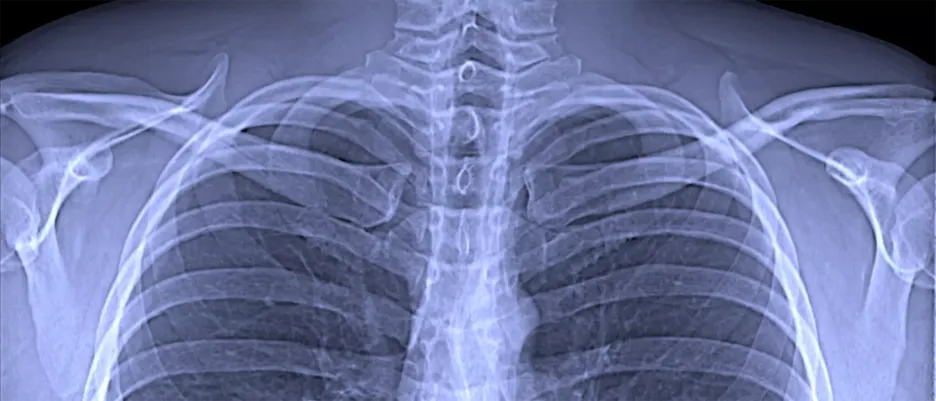

The SmartX project is researching more detailed imaging procedures in order to diagnose lung diseases better and earlier. The focus is on chronic obstructive pulmonary disease (COPD). Conventional X-rays and CT scans are often inadequate for the early detection of COPD and are associated with high radiation doses. The aim is to develop a new type of detector for the dark-field X-ray procedure that requires 50 percent less radiation dose compared to the already low-radiation procedure. An X-ray detector is the counterpart to the radiation source and produces the X-ray image. While conventional X-rays are based on the attenuation of the X-ray light, the dark-field X-ray developed at TUM uses the so-called small-angle scattering of the X-ray light. This allows additional information to be obtained about the nature of the microstructure of the lung tissue.

A research team at the Technical University of Munich (TUM) has, for the first time, produced dark-field X-ray images of patients infected with the corona virus. In contrast to conventional X-ray images, dark-field images visualize the microstructure of the lung tissue, thereby providing additional information. This approach has the potential to provide an alternative to computed tomography (CT), which requires a significantly higher radiation dose.

For the first time, researchers at the Technical University of Munich (TUM) have successfully used a new X-ray method for respiratory diagnostics with patients. Dark-field X-rays visualize early changes in the alveolar structure caused by the lung disease COPD and require only one fiftieth of the radiation dose typically applied in X-ray computed tomography. This permits broad medical application in early detection and treatment follow-up of respiratory ailments.